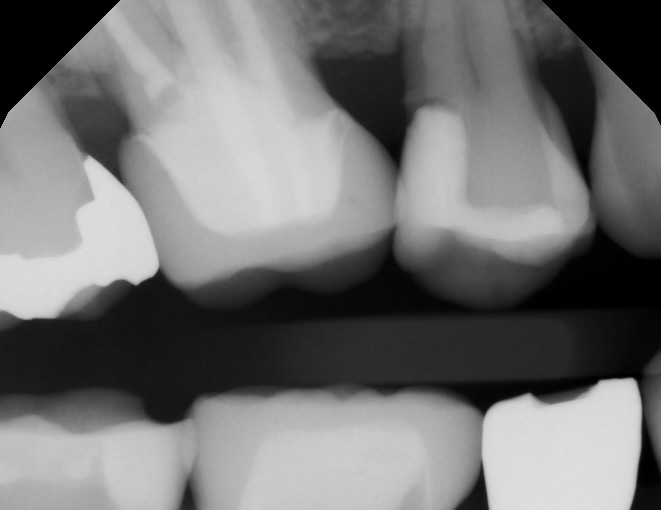

親知らずに押された7番が虫歯になってしまいました。